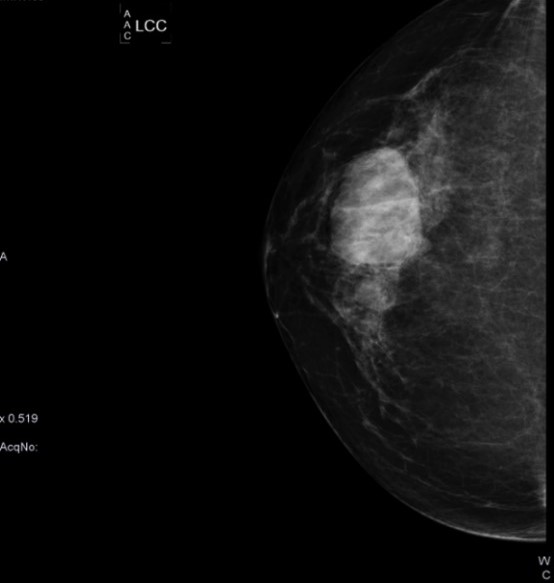

Caso 14

Una mamografía es un estudio radiográfico de diagnóstico por imágenes de las mamas, diseñado para detectar tumores y otras anomalías. Una mamografía puede utilizarse con fines de detección o de diagnóstico en la evaluación de un bulto en la mama. Desempeñan una función clave en la detección temprana del cáncer de mama y ayudan a disminuir las muertes a causa del cáncer de mama.

MÉTODO DE IMAGEN DE ELECCIÓN